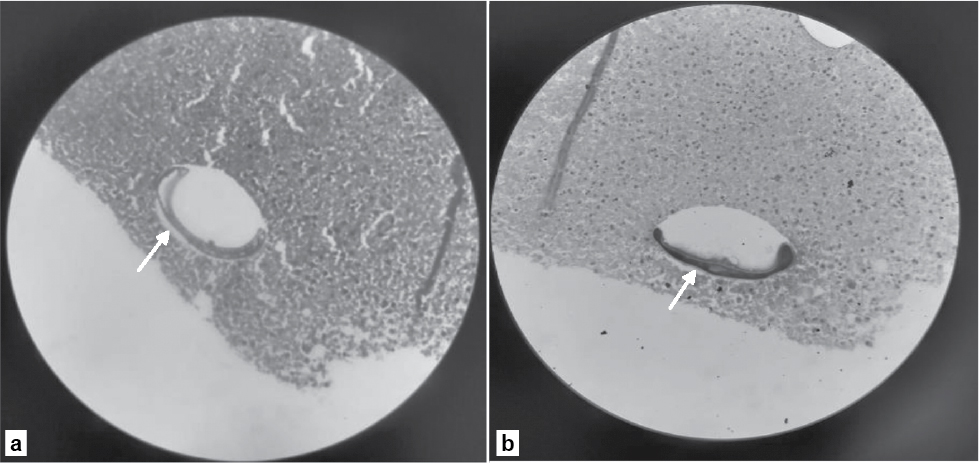

A differential diagnosis of resolving liver abscess or pancreatic pathology was considered. Further evaluation with 640-slice computed tomography (CT) abdomen showed multiple peripherally enhancing lobulated lesions with internal calcifications involving segments 6, 7 and 8 of right hepatic lobe (Fig. 1 a-f). Few lesions appeared tubular/serpiginous and were located in the subcapsular region (Fig. 2). Imaging was in favor of liver trematodes as the cause of liver abscess. A liver biopsy was done and histopathology of the tissue showed necrotic liver parenchyma with degenerated parts of parasite, likely a trematode (Fig. 3 a and b). Gram stain, acid-fast stain, fungal stain, Xpert Mycobacterium tuberculosis and tissue culture and sensitivity of the sample were negative. Since liver function tests were normal, endoscopic retrograde cholangiopancreatography (ERCP) was deferred and a decision to start medical management was taken. Patient was started on oral nitazoxanide 500 mg 3 times a day for 3 weeks. During follow-up, the patient was found to have no further fever spikes and her right upper quadrant pain had significantly reduced.

Figure 3 a and b. Histopathology of the liver showing a trematode.